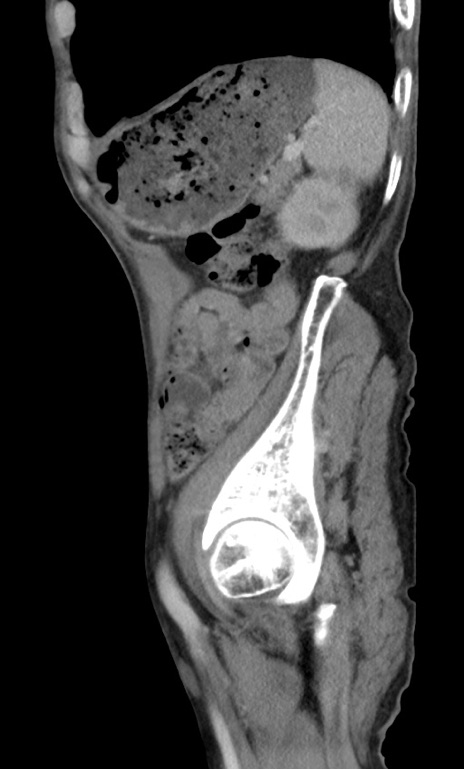

症例3(矢状断像)

冠状断像